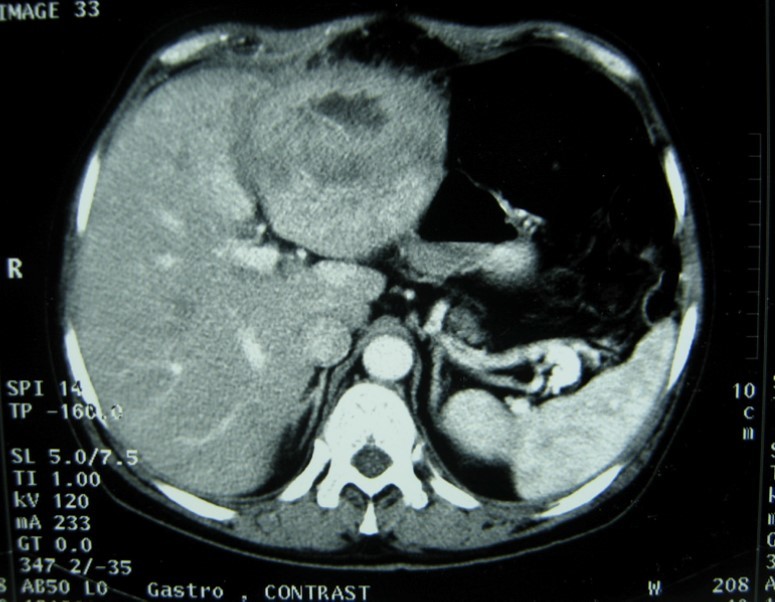

Laboratory analysis showed hemoglobin, 10.9 g/dL; white blood cell count, 9,800 cells/mm3, serum albumin, serum total bilirubin, alanine aminotransferase, aspartate aminotransferase, prothrombin time, hepatitis B surface antigen, and antibodies to hepatitis C, serum alpha-fetoprotein (AFP), carcinoembryonic antigen and carbohydrate antigen 19-9 (CA 19-9) were within normal range. Blood cultures were negative. Chest x-ray was normal. Ultrasound of abdomen showed a 10 cm hypoechogenic lesion in left liver (Figure 1). An abdominal CT showed a well-defined heterogeneous mass situated in his left hepatic lobe measuring 10 cm × 7 cm (Figure 2, Figure 3). The lesion featured central necrosis, a hyper-dense rim and a mild enrichment from the arterial phase in the CT, The diagnosis of primary hepatic tumor was suspected. An ultrasonography-guided needle biopsy of the liver was scheduled in order to rule out malignancy and to have a complete diagnosis. Cytology demonstrated a tuberculosis granuloma, acid-fast bacilli culture was positive (Figure 4). Anti-tuberculous therapy including isoniazid, rifampin, ethambutol, and pyrazinamide were prescribed. The patient completed the 6-month course of medication with success. The patient’s appetite and body weight were restored to previous levels. One year after the completion of treatment, the patient remained completely asymptomatic with disease free.

Figure 1.Ultrasonography showing a 10 cm hypoechoic lesion

Ultrasonography showing a 10 cm hypoechoic lesion

Imaging is useful for diagnosis. Abnormal chest x-rays demonstrating pulmonary tuberculosis can help for diagnosis. Our patient presented with no evidence of active pulmonary disease and the ultrasonography showed a hypoechoic rim and solitary lesion. In theses cases, it is difficult to differentiate them from carcinoma 11.